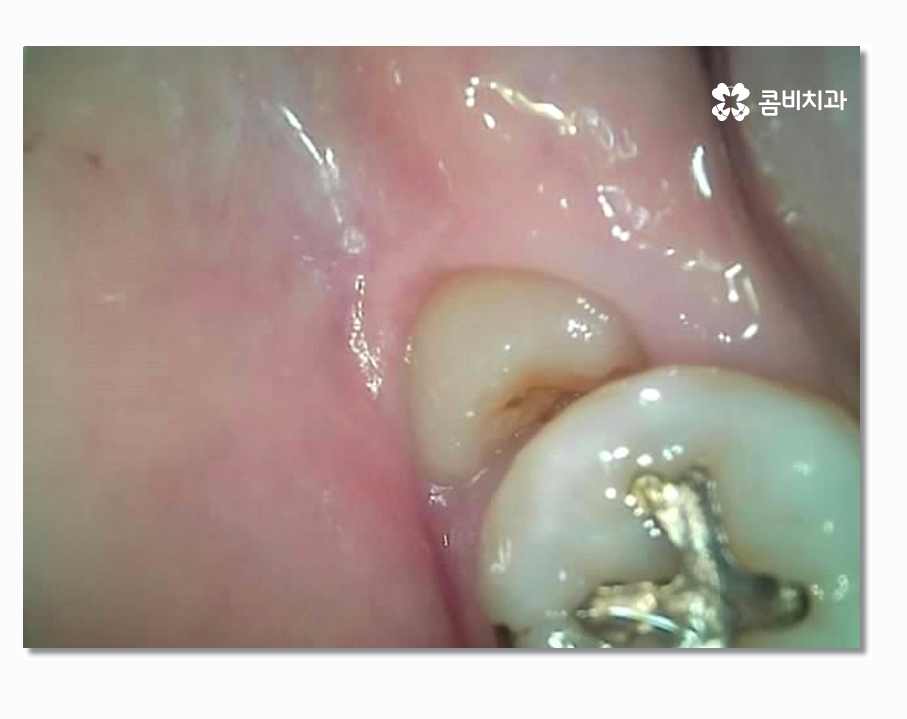

보시는 것처럼 부분매복사랑니의 경우 음식물이 끼기 쉽고

치석이 쌓이기 쉽지만 칫솔질은 어렵기 때문에

충치가 발생하여 어금니까지 함께 손상되거나

특히 잇몸질환이 발생하는 경우가 많다고 할 수 있는데요

사랑니 주변 잇몸 상태가 악화되어 치주염으로 이어지는 경우가

상당히 많은데 기본적으로는 양치가 잘되지 않아서 쌓인 치석으로 인해

치주질환에 시달리는 경우도 많지만 부분매복사랑니 처럼

치아의 상태로 인해서 염증이나 잇몸질환에 시달리는 경우도 있으므로

문제가 심해지기 전에 발치를 고려해야 할 수 있어요.